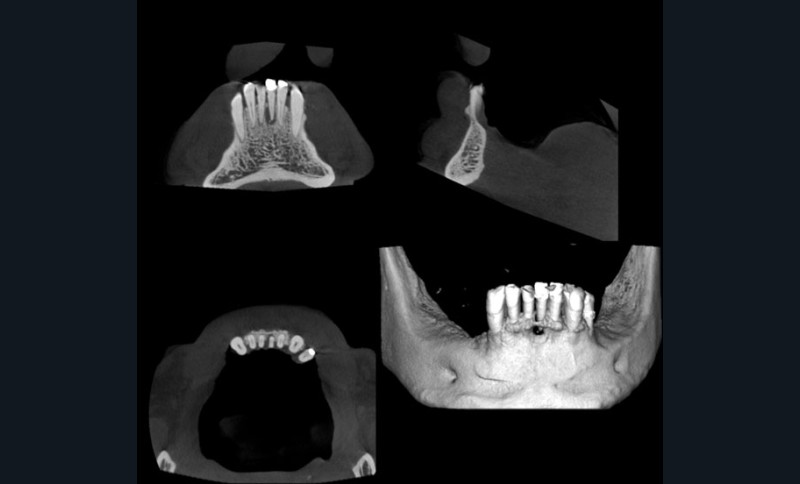

Les taux de succès des traitements endodontiques ne sont malheureusement pas toujours favorables et plusieurs études internationales ont montré des taux de traitements non satisfaisants pouvant aller jusqu’à 70 %. La prescription de plus en plus répandue d’examens « cone beam » a encore abaissé le seuil de détection d’images radioclaires apicales, ce qui augmente les indications de retraitement endodontique (fig. 1).